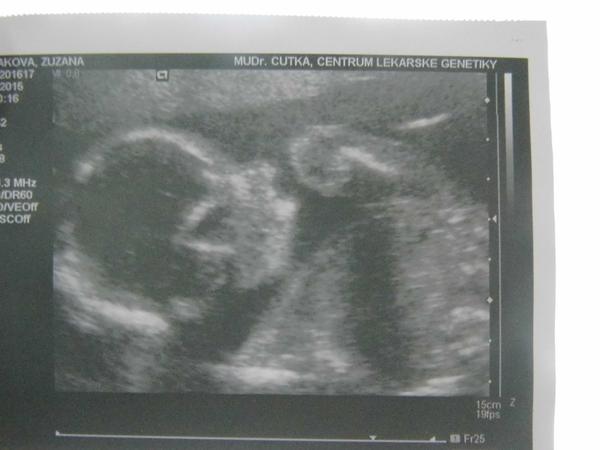

@suzik161 Já byla na měkko na NT screeningu, když nám pustil srdíčko. A moc gratuluji a přeji aby vše probíhalo tak krásně jako doposud. Já si kolem 20 týdne říkala, ještě 4 týdny a kdyby něco dokáží ho zachránit 😉